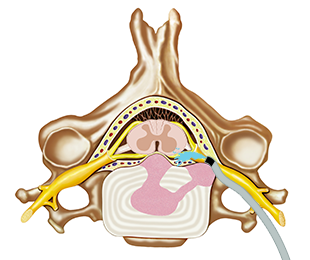

2단계

카테터가 통증 유발 부위에 도착하면 해당 부위의 유착물질을 씻어낸 후 약물을 신경염증에 직접 주입합니다.

카테터로 접근하여 신경의 유착을 풀어줌

03

1차 약물을 쏘아 각종 유착을 박리함

04

유착이 박리되고 부어있던 신경이 겉으로 드러남